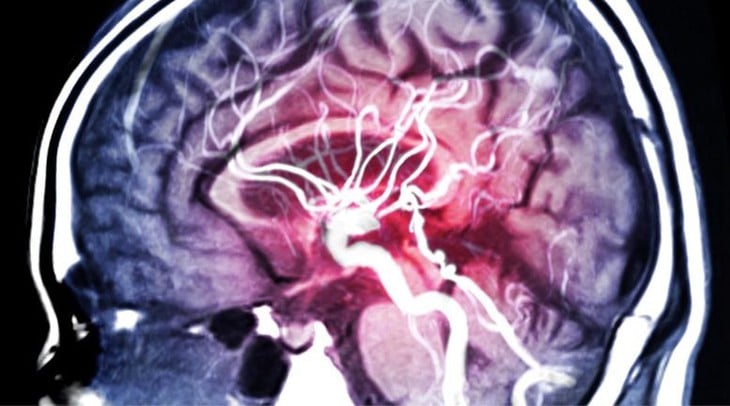

Vysoký krevní tlak tiše ničí mozek dříve, než se krevní tlak zvýší - Foto: Stock